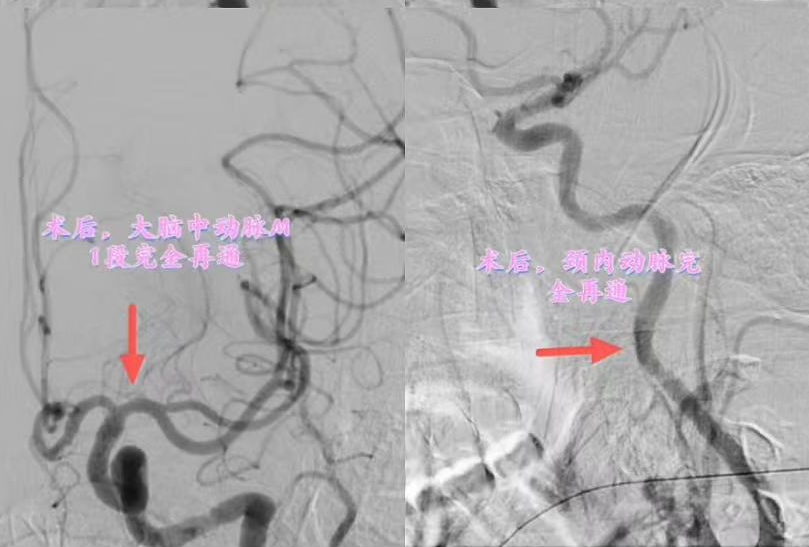

手术过程中,团队克服了患者因失语导致的躁动,采用局麻联合镇静技术。术中发现患者左侧颈内动脉起始处及大脑中动脉M1段串联闭塞,经过近两小时的努力,成功取出大量血栓,闭塞血管完全再通。

术后闭塞血管完全再通。通讯员 供图